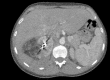

We report the case of a 29-year-old woman with Wunderlich syndrome, a rare spontaneous renal hemorrhage into the subcapsular and perinephric space. She presented to our emergency department with a sudden and persistent right flank pain in the abscence of abdominal injury. The onset of the symptoms can be insidious and lead to hypovolemic shock. Computed Tomography helps both in the diagnosis, detecting the renal hemorrhage, and contributes to an optimal patient management. Selective arterial embolisation is an efficient technique to stop acute and potential life-threatening hemorrhage and preserve the renal parenchyma.